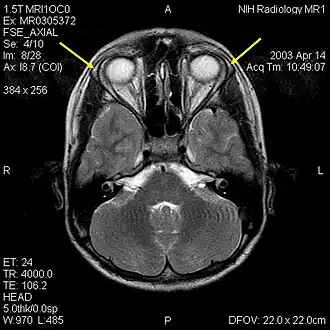

MRI мозга 12-летнего подростка с тройным синдромом видны гипопластичные слезные железы (желтые стрелки)